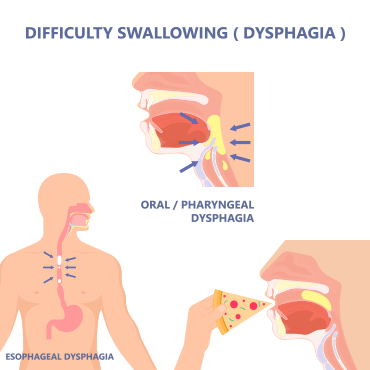

Gastroenterology

OMI’s Gastroenterology Department provides a one stop service dedicated to complex disorders of digestive tract, liver, pancreas and biliary system. OMI is one of the few hospitals in Karachi where highly experienced team of gastroenterologists provide comprehensive emergency services round the clock. The endoscopy unit caters to all kinds of endoscopic procedures including endoscopic retrograde cholangiopancreatography (ERCP), biliary and pancreatic duct stenting, and common bile duct (CBD) stone removal procedures.